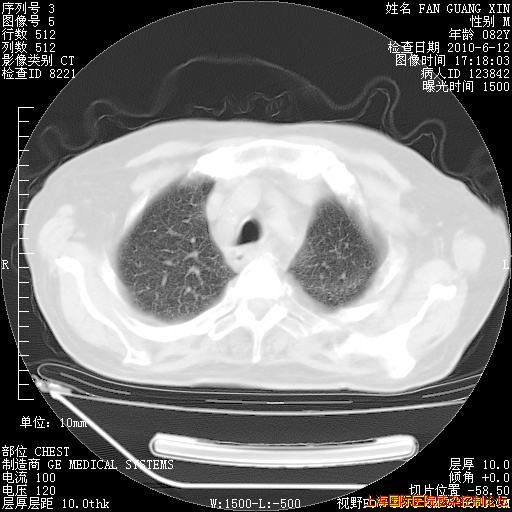

今天复查CT

今天CT

整整相隔30天的肺部CT好像有所好转啊。甲强龙减量第3天,需要观察体温。

海管,自昨日你和我通完话后,不知您岳父消化道症状有无缓解?体温怎样?阅读7.12日胸部ct,个人认为目前激素治疗是有效的,甲强龙减量是适宜的。因在抗痨治疗,需密切观察肝功、肾功能和血常规。不过,老年、长期住院和大量使用激素,很担心菌群失调发生